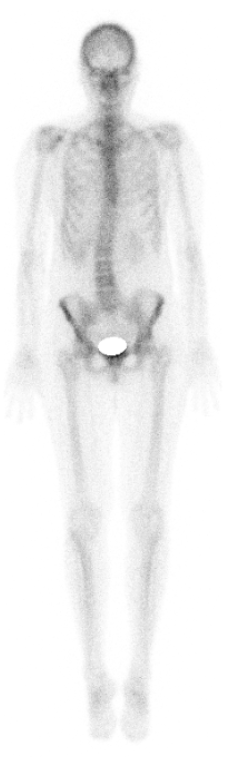

PET/CT

mit Ga68-/F18-PSMA, Ga68-DOTA oder F18-FDG

Ähnlich dem SPECT/CT markiert die PET/CT momentan die Spitze der modernen (Hybrid-)Bildgebung. Technisch treffen sich hier in einem Gerät zwei Welten: Das PET (PositronenEmissionsTomographie) aus der Nuklearmedizin zur Darstellung von Zell-/Körperfunktionen ist mit einem CT (ComputerTomographie) aus der Radiologie zur Darstellung von Anatomie kombiniert.

Mit dieser tollen Methode können sehr umfassend Fragen aus den Bereichen Tumor-, Neuro- oder Entzündungsdiagnostik beantwortet werden.